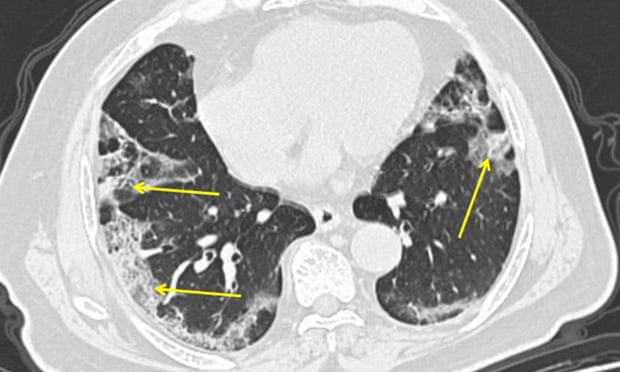

Tomografía computarizada de un hombre con Covid-19. La neumonía causada por el nuevo coronavirus puede aparecer como parches nebulosos en los bordes exteriores de los pulmones, indicados por flechas. Fotografía: Hospital Mount Sinai / AP

De acuerdo a Wilson, la neumonía que nace del Covid-19 comienza con una infección que llega al árbol respiratorio. Es decir, a los conductos que conducen el aire del exterior a los pulmones.

"Lo que viene después es que el revestimiento del árbol respiratorio se lesiona, causando inflamación. Esto a su vez irrita los nervios en el revestimiento de las vías respiratorias. Si esto empeora, la inflamación entra a las unidades de intercambio de gases y si estas se infectan, el material inflamatorio alcanza los alvéolos, que son el fondo de nuestros pulmones".

Los alveolos son diminutos sacos de aire en las terminaciones de los bronquiolos, son la última parada de las ramas del árbol respiratorio humano. Es aquí donde los pulmones y el torrente sanguíneo intercambian dióxido de carbono y oxígeno.

Si los sacos de aire se inflaman, dice Wilson, esto provoca una "efusión de material inflamatorio [líquido y células inflamatorias] en los pulmones y terminamos con neumonía". Esto hace que el torrente sanguíneo no pueda recibir suficiente oxígeno, reduciendo función primaria de los pulmones, que es la capacidad de tomar oxígeno y eliminar el dióxido de carbono.